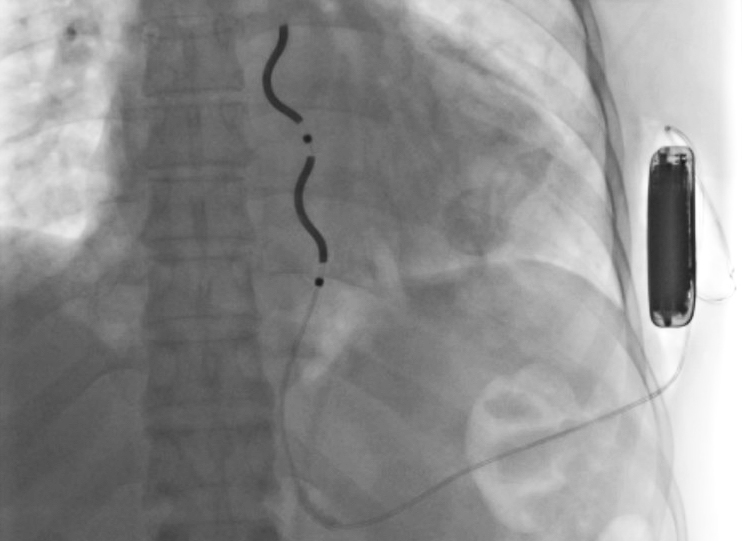

W Miejskim Szpitalu im. Strusia w Poznaniu przeprowadzono innowacyjny zabieg kardiologiczny. 47-letni mężczyzna, u którego często dochodziło do zatrzymania krążenia, otrzymał automatyczny kardiowerter-defibrylator. Lekarze wszczepili pacjentowi urządzenie pod skórę, w okolicy lewej pachy.

Operacja - Miejski Szpital im. Strusia

Fot. Miejski Szpital im. Strusia

Tego typu defibrylator nie wymaga umieszczenia elektrody wewnątrz komory serca. Jest wszczepiany pod mostkiem, poza sercem. Dzięki temu pacjent unika powikłań, jakie mogą się pojawić, gdy elektroda jest wprowadzana za pośrednictwem układu żylnego.